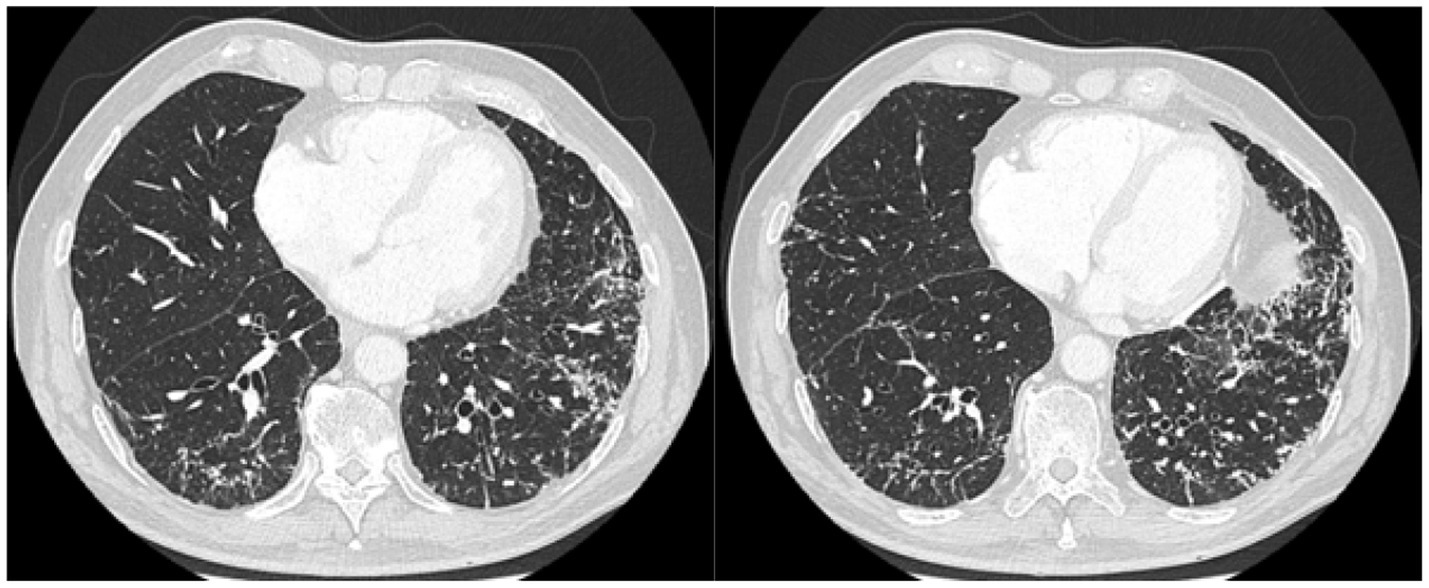

High-resolution computed tomography of the chest showed a pattern of dendriform nodular ossification suggested by multiple micro-nodules, most calcific, with dominance in the lower lobes and micro-nodules organized in clusters and aggregates along interlobular septa resulting in a “coral like” form (Figure 1). Abdominal contrast CT scan showed irregular pancreas with diffuse calcifications (Figure 2). A 99mTc-MDP scan performed showed pathological accumulation of radiopharmaceutical.

Figure 1

Lung CT scan: several micronodules, linear and branching, predominant in the lower lobes, with sublymphatic distribution and along the bronchovascular axis; most of these are calcific.